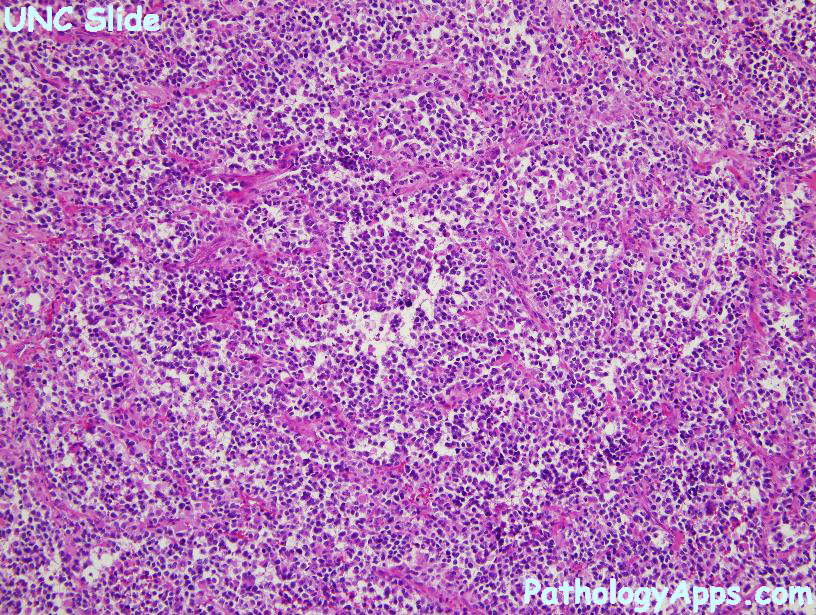

Alveolar Rhabdomyosarcoma Pathology

pathologyapps.com

pathologyapps.com